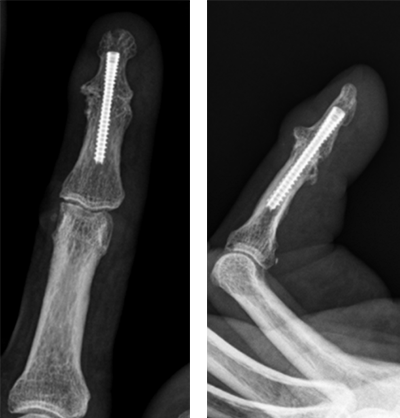

へバーデン結節に対しては、スクリューによる関節固定術を行います。DIP関節が動かせなくなりますが、痛みの改善が期待されます。

へバーデン結節に対する関節固定術